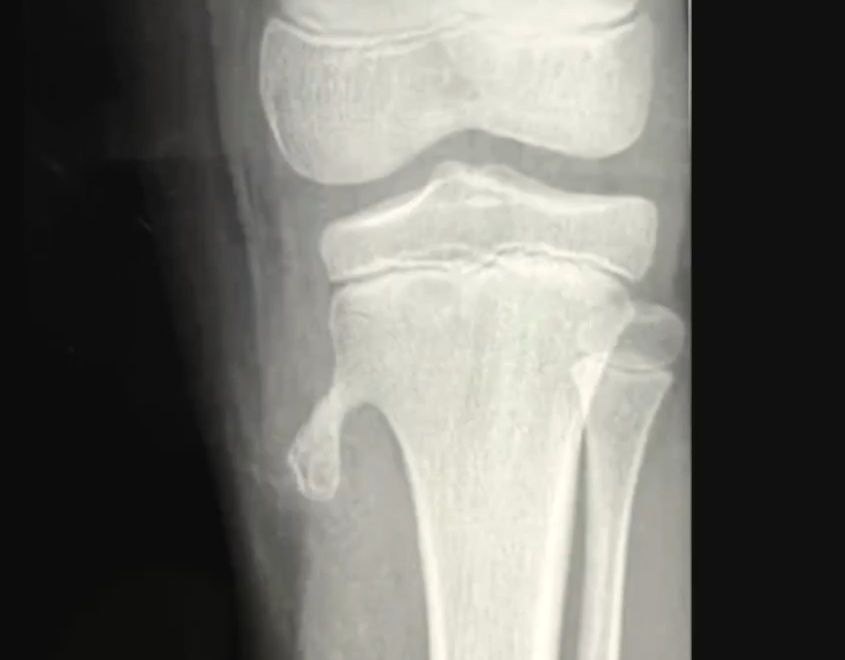

Если каллус начнет буквально вытекать во внекостное пространство, то стекать он будет вниз, и на картинке это хорошо видно. Так формируется как будто отдельная косточка рядом с большой.

Костная мозоль

Когда мы говорим про каллус, костную мозоль после ремоделирования, то мы должны понимать, что кость в этой зоне всегда толще, она всегда плотнее, то есть присутствует характерное увеличение толщины костной ткани, потому что у нас всегда присутствует усиление структуры в стадии исцеления. На этом же месте сломать кость будет очень сложно, практически невозможно. Можно сломать чуть выше, можно сломать чуть ниже, но вот там, где уже сформировалась костная мозоль, это практически невозможно. В этом процессе принимает участие множество клеток – конечно же, остеобласты, которые будут заниматься кальцификацией.